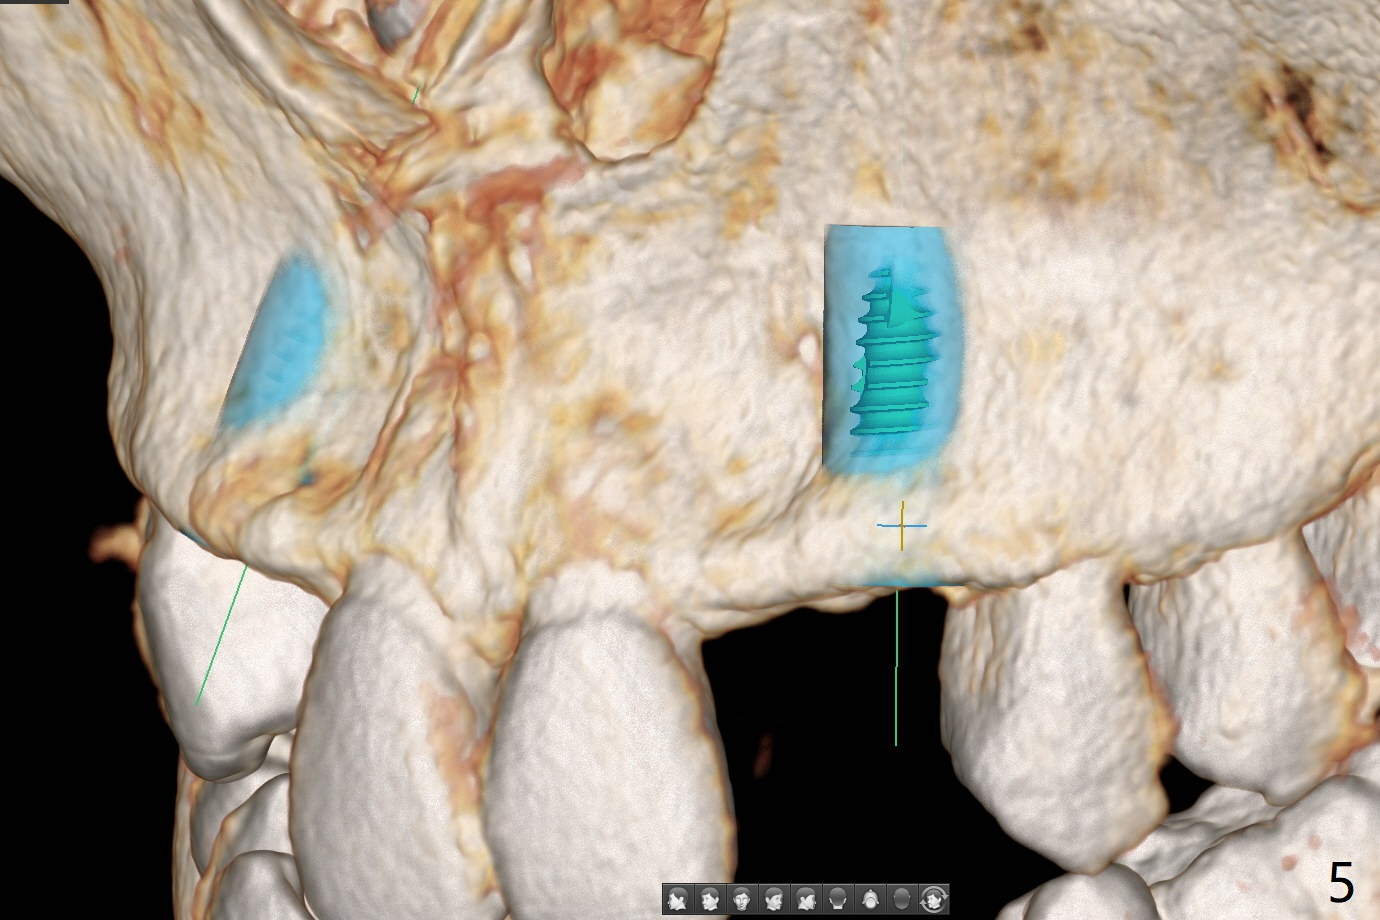

18岁男先天缺失上颌2,3(图一:双侧),2严重颊侧骨壁凹陷(图二,三:2),准备在两侧3种植(图二,三:绿色),做悬臂桥,右上植体3.5乘10毫米,但是必须用带有角度基台修复。而左上3用同样大小植体,颊侧螺纹暴露(图三 B),你会怎么处理?一个月病人到外州上学,而且治疗必须在十九岁前完成,保险可多付钱。为了能在颊侧植骨(图四红圆圈),在左上1近中做一个垂直切口(图五,六红实线),潜行分离骨膜直到4近中(红虚线),并且放置骨块,让骨膜离开颊侧骨板,钻洞时不损伤骨膜。植体放入后,检查颊侧骨块是否足够,最后放置PRF膜,缝合。